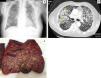

Our patient was an 85-year-old man with pure red cell aplasia who had been receiving steroid treatment (prednisone 1mg/kg/day) for 5 weeks. He was admitted for 5-day history of dyspnea and chest pain. The chest radiograph revealed a diffuse, bilateral micronodular pattern (Fig. 1a) that was not observed on the radiograph obtained 2 weeks before admission. Chest computed tomography was performed, revealing bilateral pulmonary nodules, some of which were cavitary, and which tended to coalesce in the upper lobes (Fig. 1b). The patient developed severe respiratory failure that did not respond to empirical antibiotic treatment plus voriconazole, and died 6 days after admission. Gross autopsy findings included multiple cavitary nodules of different sizes, with thickened walls, containing purulent material (arrows), distributed diffusely in both lungs (Fig. 1c). Aspergillus ustus was isolated from cultures of the material obtained from these lesions. The final post-mortem diagnosis was invasive pulmonary aspergillosis caused by Aspergillus ustus in an immunocompromised patient.